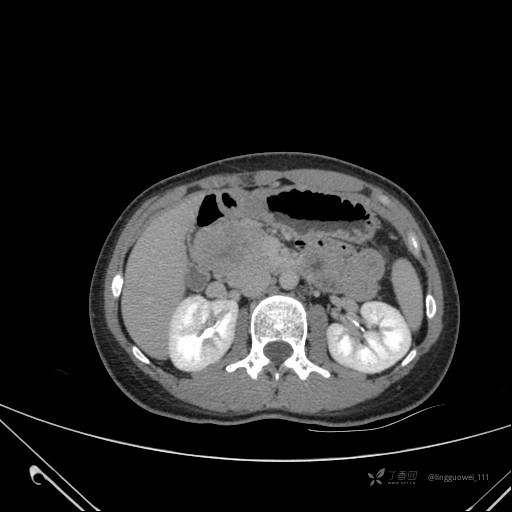

患者性别:女

患者年龄:28岁

主诉:体检发现胰腺病变,行 CT检查。

平扫: